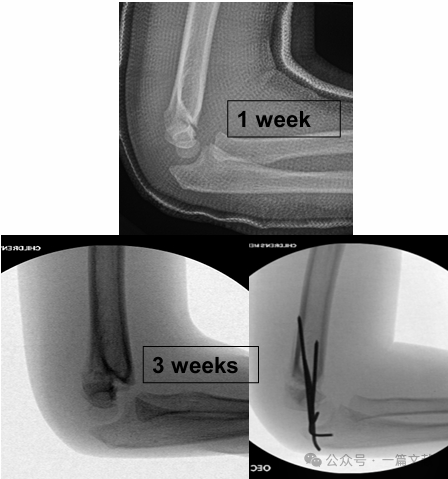

IV. Non-Operative Treatment: Avoid casting the swollen elbow in greater than 90 degrees of flexion. Close follow-up is essential, especially for Type 2 fractures. If treated with closed reduction alone, the loss of reduction rate can be as high as 48% within the first week. Risk factors for displacement include: greater initial displacement, Type 2B fractures, and patients with larger upper arm circumference. As shown in the figure, a patient treated conservatively had fracture displacement on follow-up X-ray at 3 weeks and subsequently underwent surgical fixation with K-wires.